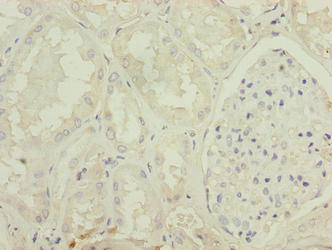

Immunohistochemistry of paraffin-embedded human kidney tissue using CSB-PA11869A0Rb at dilution of 1:100